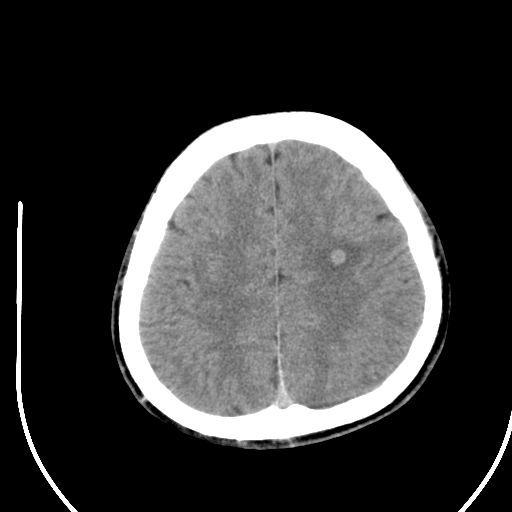

标题: CT28158:男,27Y。头痛数月,左顶叶血管瘤。 [打印本页]

标题: CT28158:男,27Y。头痛数月,左顶叶血管瘤。

考虑avm。

考虑avm。  建议dsa检查。

海绵状血管瘤

考虑左顶叶海绵状血管瘤,建议mr检查。

左侧额叶海绵状血管瘤可能性大;建议行mri检查。

考虑血管畸形,因其周可见水肿,不除外感染性病灶。建议mri检查。